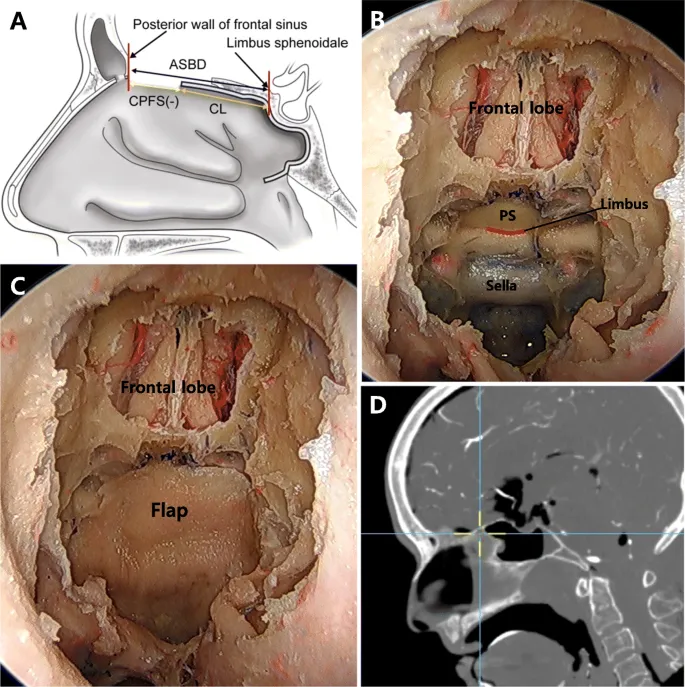

- Pericranial Flap (PCF)

- Artery: Supraorbital & supratrochlear aa.

- Uses: Large anterior cranial fossa defects. Open/endoscopic harvest.